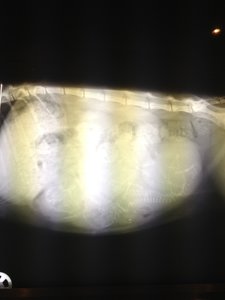

so hier die bilder

Anhänge

• 003.JPG

003.JPG

1,9 MB · Aufrufe: 15

• 013.JPG

013.JPG

1,7 MB · Aufrufe: 28

• 012.JPG

012.JPG

1,5 MB · Aufrufe: 21